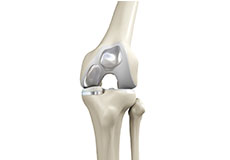

Total Knee Replacement

Total knee replacement, also called total knee arthroplasty, is a surgical procedure in which the worn out or damaged surfaces of the knee joint is removed and replaced with an artificial prosthesis.

Knee Implants

Knee implants are artificial devices that form the essential parts of the knee during a knee replacement surgery. The knee implants vary by size, shape, and material. Implants are made of biocompatible materials that are accepted by the body without producing any rejection response. Implants can be made of metal alloys, ceramic or plastic, and can be joined to the bone.